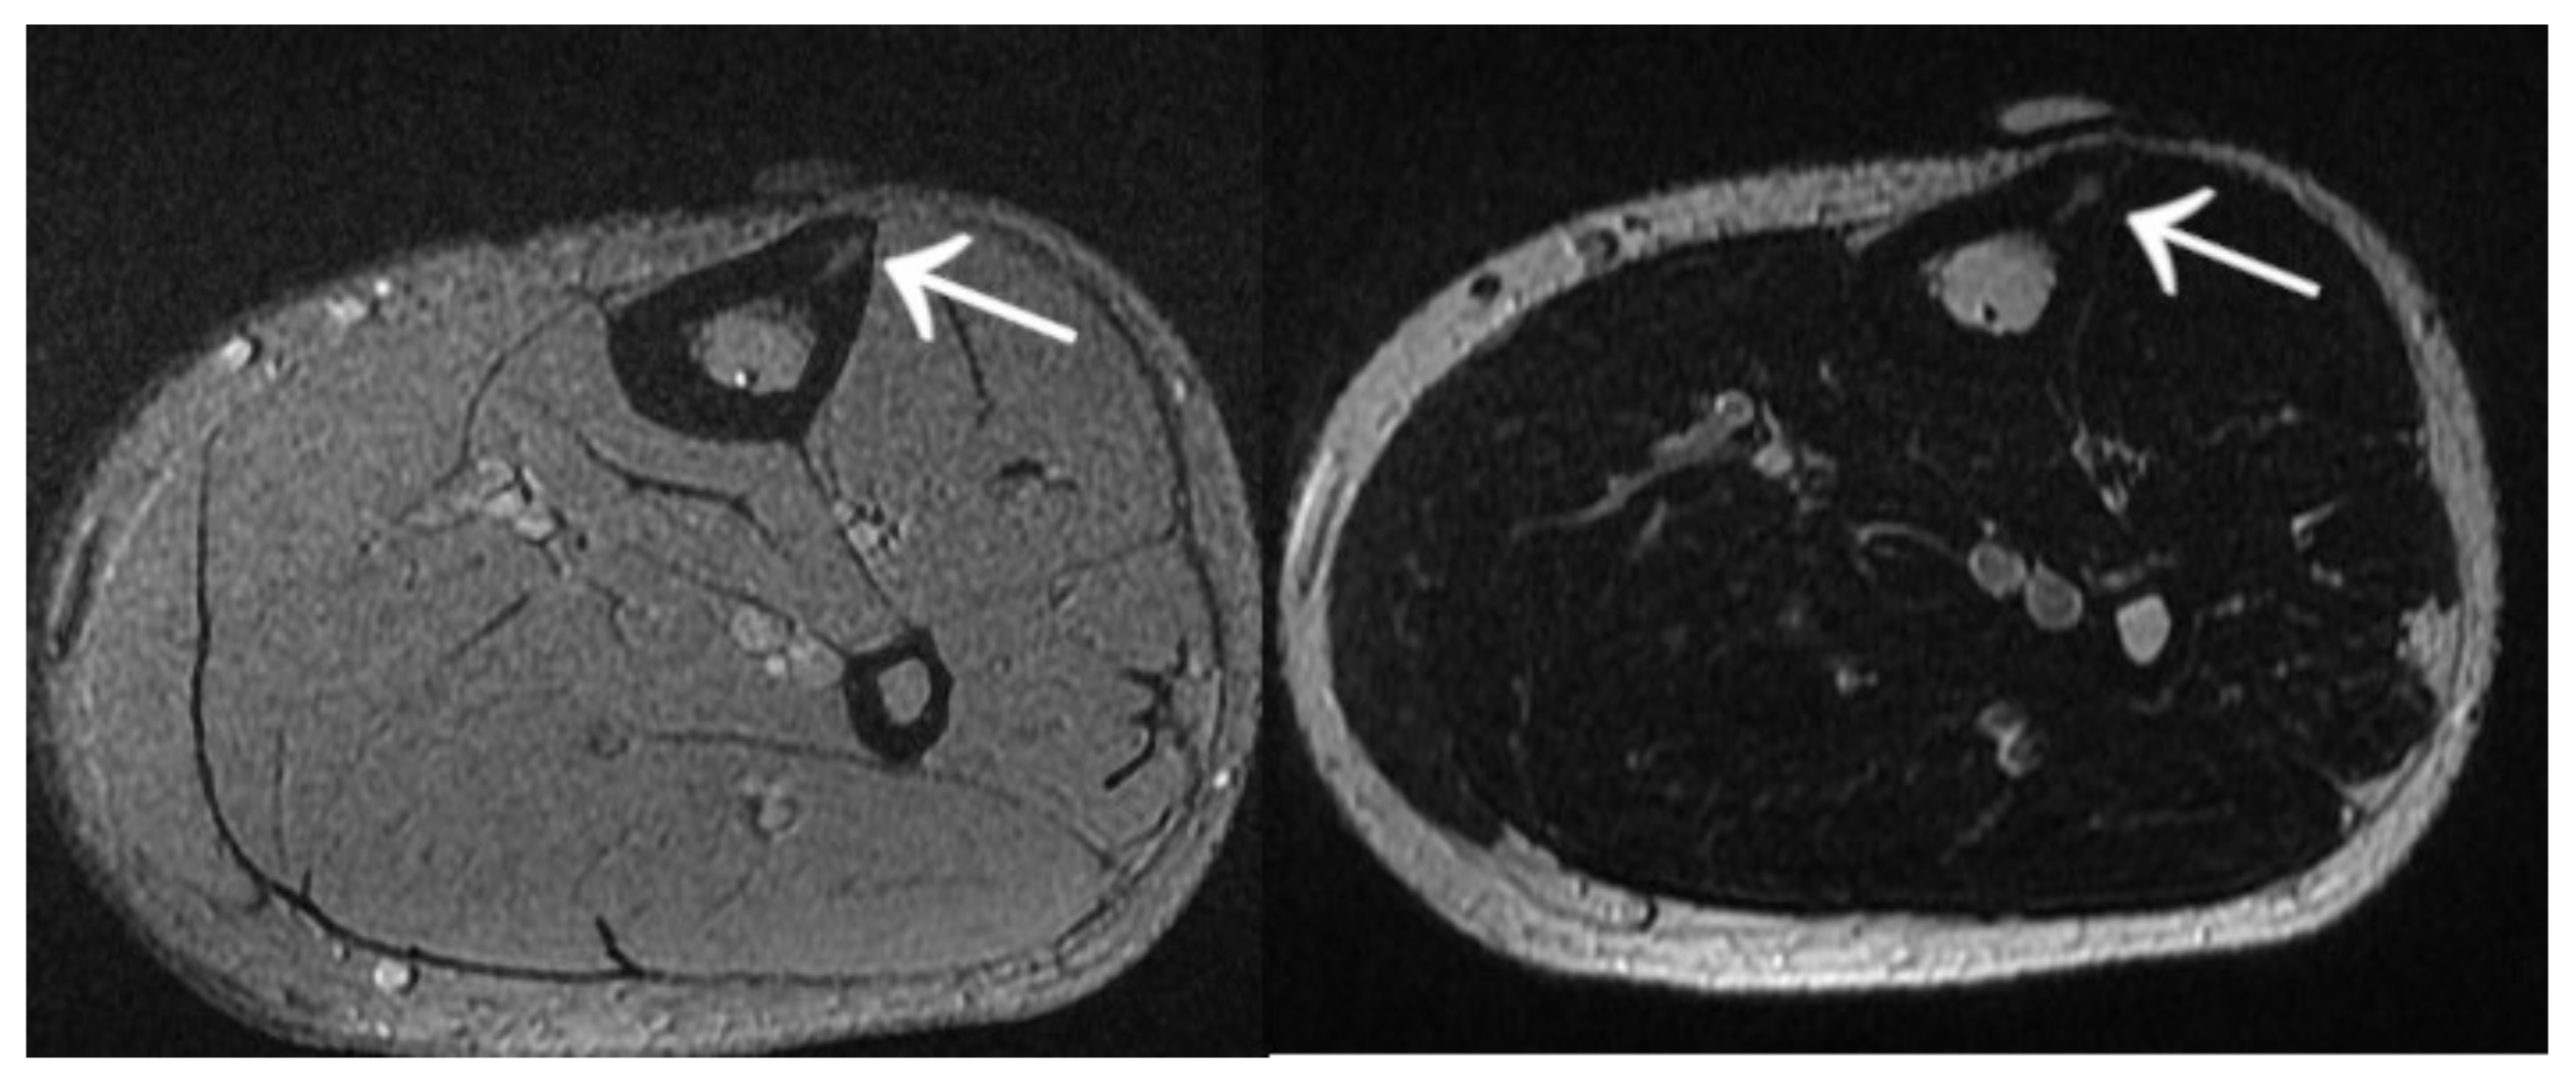

3.7. Case 7: OO Masking as a Meniscus Injury